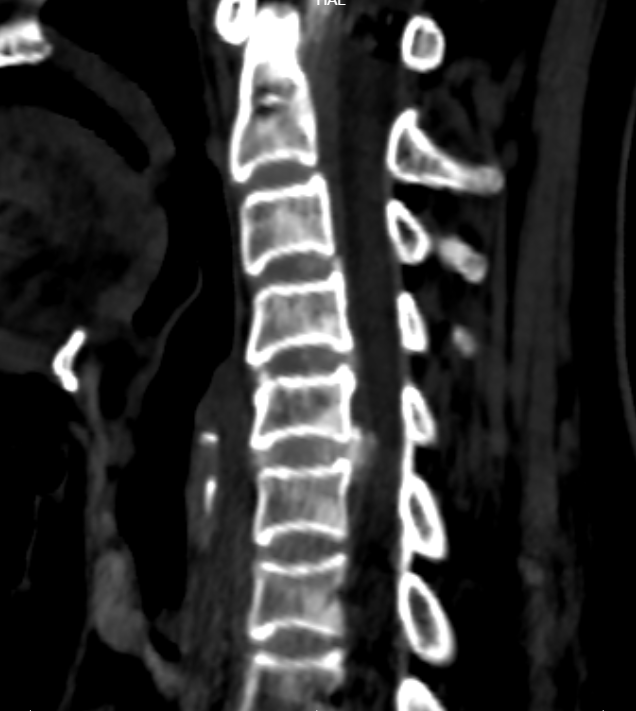

患者李女士,68岁,反复颈部疼痛并四肢麻木3月,影像学检查后确诊为脊髓型颈椎病,C5/6椎间盘突出伴颈髓损伤,保守治疗无效。脊柱外科钟炯彪主任根据患者病情制个体化治疗方案,由于C5/6椎间盘突出部位已出现钙化并有可能与硬膜粘连,手术难度骤增,因此脊柱外科决定采用3D外视显微镜辅助对该患者实施颈椎ACDF术。

术前影像-MRI/CT

本次手术由钟炯彪主任医师主刀,团队成员高效协作,借助3D外视镜高清显微成像,术者通过佩戴3D眼镜直视屏幕操作,术野清晰立体,“层层解剖”,大幅提升了操作的舒适度与精准度。手术在清晰立体的视野下,术者能准确完成病变椎间盘切除、脊髓减压及椎间融合、钛板螺钉固定等关键步骤,出血量较平常减少超50%,神经周围操作精细,极大降低了并发症的发生。

患者术后顺利康复,四肢麻木乏力症状明显减轻。术后第2天即佩戴颈围下床活动,活动自如,复查影像学显示内固定满意,术后第5天即出院。